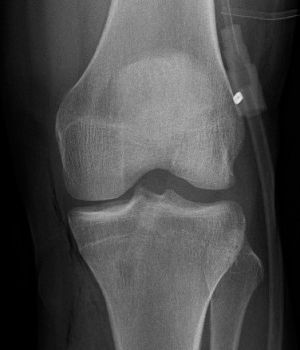

Im Röntgenbild zeigt sich nach der Operation eine regelrechte Positionierung der Bohrkanäle im Knochen sowie das Fixationsmaterial im Bereich des Oberschenkels (Plättchen) und im Bereich des Unterschenkels (Schraube).